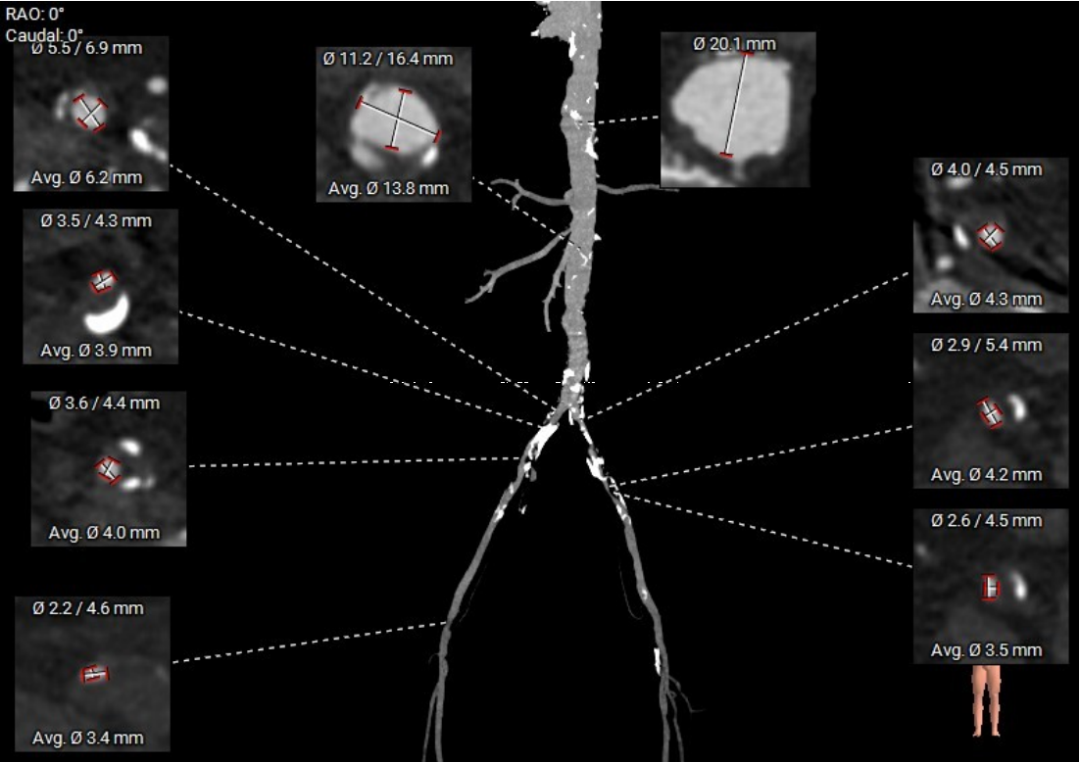

术前CT评估

入路分析:

走形平顺,但主动脉全程多发溃疡样病变,伴夹层及壁内血肿形成;双髂股动脉内径偏小,右侧最小内径2.2mm,左侧最小内径2.6mm,右侧合并血肿及夹层。

左侧颈总动脉走形、内径均可,少量钙化;左右侧锁骨下动脉内径小,最狭窄处分别4.3mm、4.2mm,且伴有不同程度血肿。